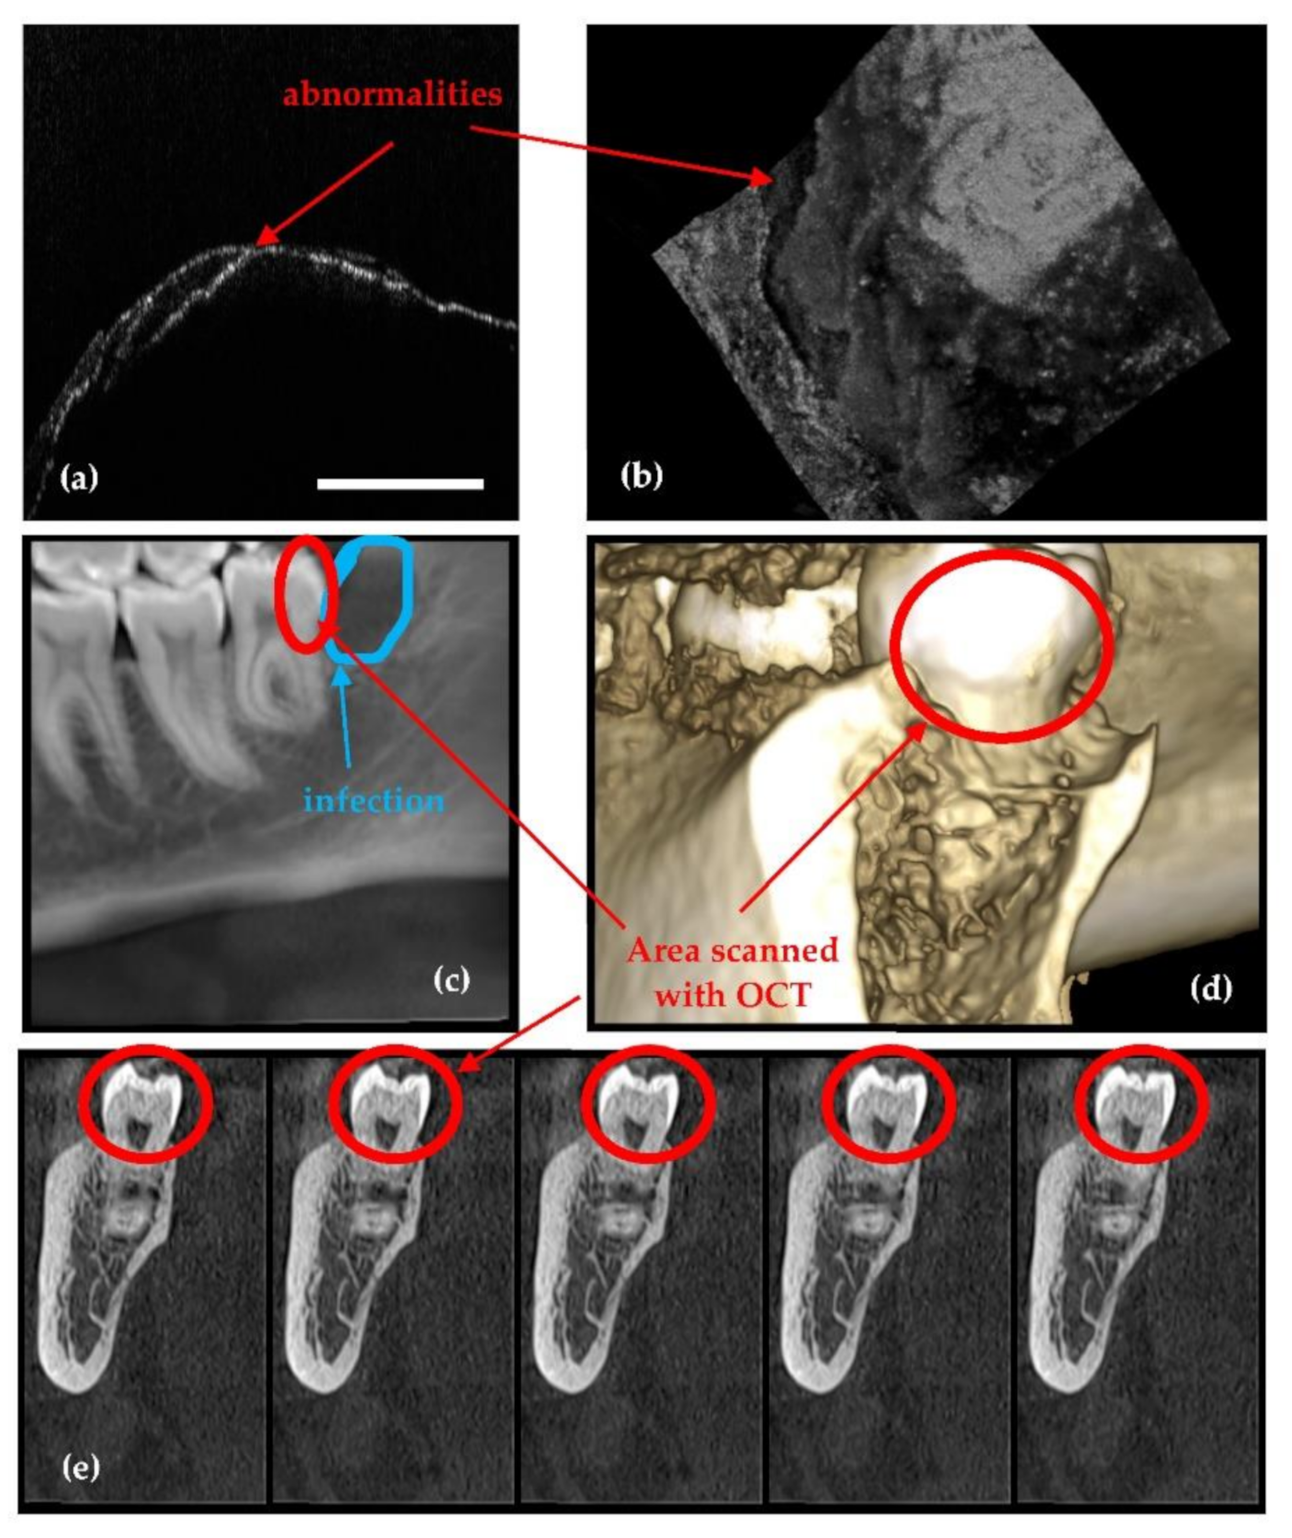

2.5. OCT versus Radiography

- Because it is using IR laser radiation, OCT does not penetrate metals, although studies of their roughness can be made [46] and, as shown in Figure 4, OCT can provide images near dental crowns, while 3D CBCT for example cannot achieve such images. Also, we have demonstrated that OCT can replace the gold standard of SEM in the study of metallic fractures [47,48]. Therefore, a subject of future work in our groups refers to OCT studies of metallic parts included in the oral cavity, for example dental implants.